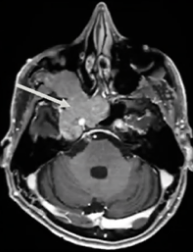

患者術(shù)前影像。(A)術(shù)前軸位T1加權(quán)釓增強(qiáng)磁共振成像(MRI),顯示腦膜瘤延伸至后顱窩、海綿竇、眼眶和蝶竇。(B)腫瘤延伸至中顱窩、翼腭窩和顳下窩。(C)術(shù)前軸位計(jì)算機(jī)斷層掃描(CT)顯示蝶骨大翼侵蝕和蝶竇受累。